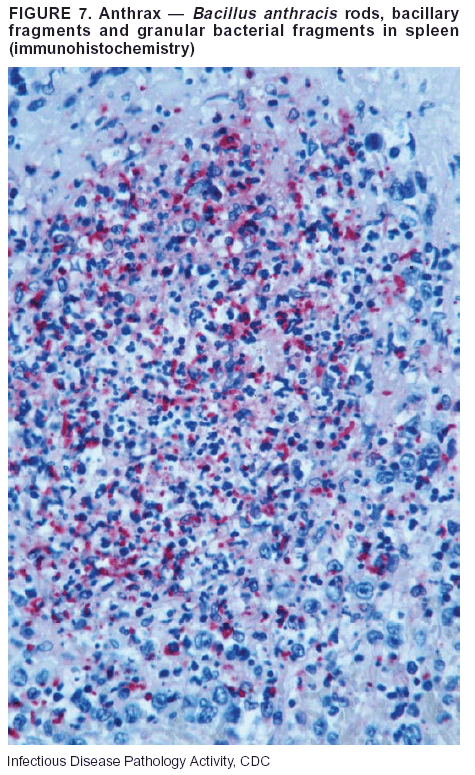

Pathologic Findings. Anthrax has three pathologic forms. Cutaneous anthrax is characterized by an eschar that forms where the bacteria entered the skin (Figure 2). Microscopically, the epidermis has necrosis and crusts, whereas the dermis demonstrates necrosis, edema, hemorrhage, perivascular inflammation, and vasculitis. The lymph nodes that drain the skin site eventually become enlarged, necrotic, and hemorrhagic. Gastrointestinal anthrax is distinguishable by hemorrhagic ulcers in the terminal ileum and caecum accompanied by mesenteric hemorrhagic lymphadenitis and peritonitis. Inhalational anthrax is characterized by hemorrhagic mediastinal lymphadenitis (Figure 3) accompanied by pleural effusions. Histologically, lymph nodes have abundant edema, hemorrhage, and necrosis with limited inflammatory infiltrate (Figure 4) (18,25--29). As any of the three anthrax forms progresses, the bacteria can spread to abdominal organs, producing petechial hemorrhages, and to the central nervous system, producing hemorrhagic meningitis (i.e., cardinal's cap) (Figure 5).

Diagnostic Specimens. Performing a complete autopsy with histologic sampling of multiple organs will help determine the distribution of bacilli and the portal of entry. The specimens that harbor the highest number of B. anthracis organisms vary by the pathologic form of anthrax. For example, diagnosis of cutaneous anthrax requires skin samples from the center and periphery of the eschar, whereas for inhalational anthrax, pleural fluid cell blocks, pleura tissue, and mediastinal lymph nodes have the highest amounts of bacilli and antigens.

Diagnostic Tests. If the patient has not received antibiotics, bacilli can be observed in tissues with H&E, Gram, and silver impregnation stains and IHC assays (Figures 6 and 7). However, after antibiotic treatment has been instituted, only silver stains and IHC assays will highlight the bacilli. IHC assays for B. anthracis can demonstrate bacilli, bacillary fragments, and granular bacterial fragments in formalin-fixed tissues, even after 10 days of antibiotic treatment. Although a DFA test is available for B. anthracis, it is not used on formalin-fixed tissues.